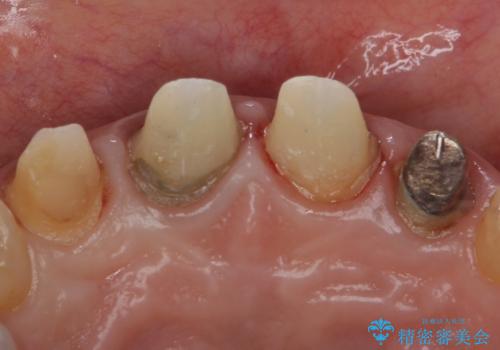

自然な前歯にしたい ジルコニアクラウンでの修復

- 前歯を綺麗にしたいとのことで来院されました。

色調・適合ともに改善するために一度被せ物を外し、歯の形を整えた後に新しい被せ物を装着していきます。

- 右上12左上12/仮歯4本+ジルコニアクラウン4本:44,000+484,000円 左上2/根管治療(保険)費用は治療当時の料金となります

歯ぐきの炎症を抑えつつ、被せ物と歯との境目がわからなくなるよう被せ物を装着しました。

審美性が大変改善されたことで患者様にもご満足いただけました。